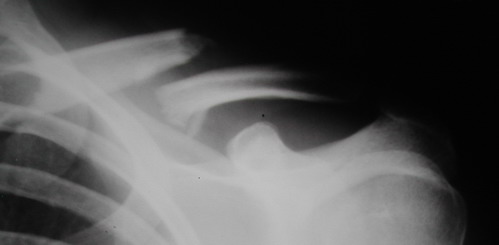

В приложении проект наших тезисов на съезд и клинический пример: Пациентка 23 лет поле неэффективного оперативного лечения (4 нед.) перелома ключицы спицей (была оперирована в С-Петербурге)(снимок после удаления спицы) и результат закрытого БИОС..

Один из вариантов, что удалось быстро найти, позже еще найду, но схема примерно такая (первое

вложение).

Мужик кочегар, срок нетрудоспособности 7 недель. Наружную конструкцию сняли через 3 недели. Далее без иммобилизации. Погруженную спицу можно убрать и через несколько месяцев, если жить не мешает.

Раньше не погружали, на рентгенограммах и натуре видно (последние 2 вложения). Как вариант спицы в периферическом отломке могут крепится на трехдырочную приставку, что дает возможность компрессии.